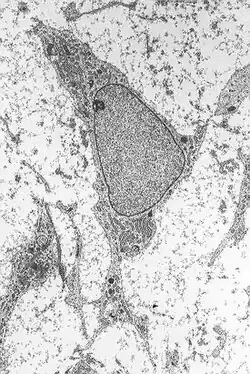

The proposed method involved converting mesenchymal stem cells—normally destined to become bone or adipose tissue—into neurons through brief exposure to retinoic acid diluted in ethanol.[15] The procedure consisted of extracting cells from the patient's bone marrow, exposing them in vitro to an 18 micromolar solution of retinoic acid for two hours, and subsequently reinfusing them into the same patient.[16]

In early 2012, inspections by the Carabinieri’s Anti-Adulteration Unit and the Italian Medicines Agency revealed numerous violations of hygiene and safety regulations. Essential legal documentation was missing, and the treatments lacked effective concentrations of mesenchymal stem cells. The cells were unable to differentiate into neurons and contained hazardous contaminants. Based on an analysis of the medical records of 36 patients, no clinical improvement was observed—except for three cases, judged solely on subjective assessments. Following these findings, the Stamina treatments at the Brescia hospital were suspended.[28]

The rejection was based on several issues: the application lacked sufficient methodological details, it claimed a cell differentiation process that was deemed implausible given the extremely short incubation time (between 40 minutes and 2 hours), and the observed morphology of the supposed nerve cells could have resulted from cytotoxic effects rather than genuine differentiation.[16]